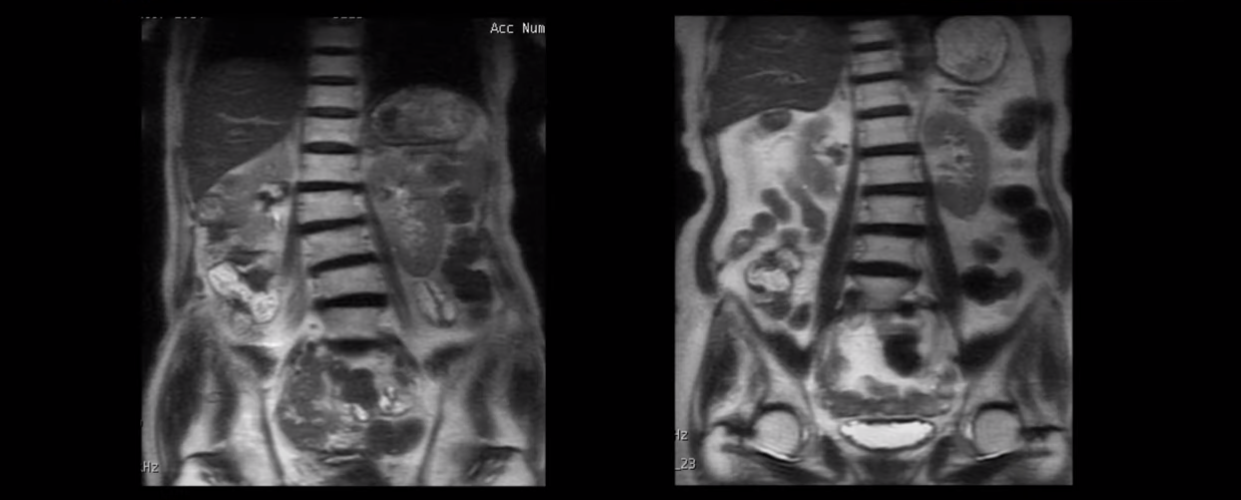

근육이 늙는다는 건 나이가 들면서 근육이 줄어들며 약해지고, 또 이런 근육 상태로 일을 하고 운동을 하니까 결국 근육이 망가지고 뭉치고 뒤틀린다는 걸 말합니다. 그래서 70대 이상 협착증 환자를 척추를 보면 척추가 반듯한 분이 단 한 명도 없습니다.

전부 다 척추가 틀어지고 심하게 휘어져있습니다. 허리 주변 근육이 다 뒤틀려있다는 얘기입니다.

보시다시피 근육도 많이 줄어들어 심하게 작아져 있습니다. 이게 바로 근육에 심한 문제가 있다는 증거입니다.